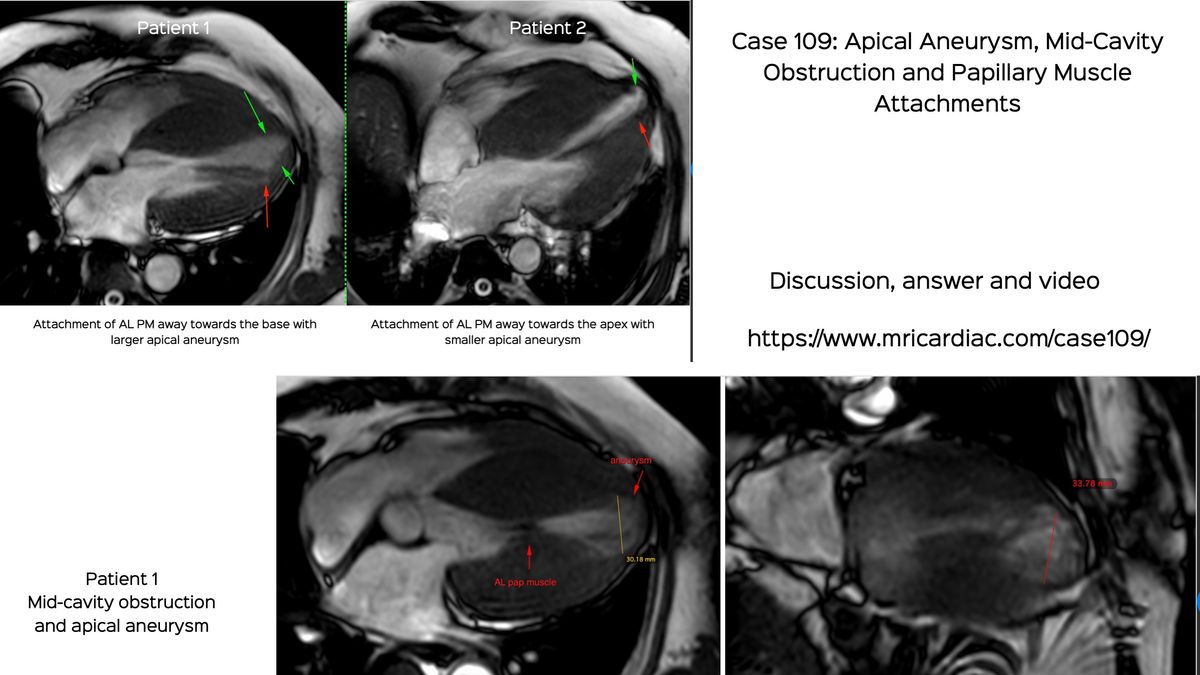

Case 109: Apical Aneurysm, Mid-Cavity Obstruction and Papillary Muscle Attachments

It is important to understand and diagnose apical aneurysms, infarcts, mid-cavity obstruction and associated changes